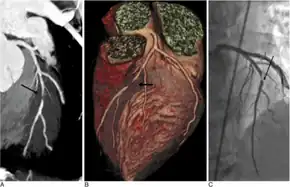

a) Curved-planar maximum-intensity projections b) three-dimensional volume rendering technique reconstructions of left anterior descending artery c) stenosis of right coronary artery

For symptomatic people, stress echocardiography can be used to make a diagnosis for obstructive coronary artery disease.[60] The use of echocardiography, stress cardiac imaging, and/or advanced non-invasive imaging is not recommended on individuals who are exhibiting no symptoms and are otherwise at low risk for developing coronary disease.[60][61]